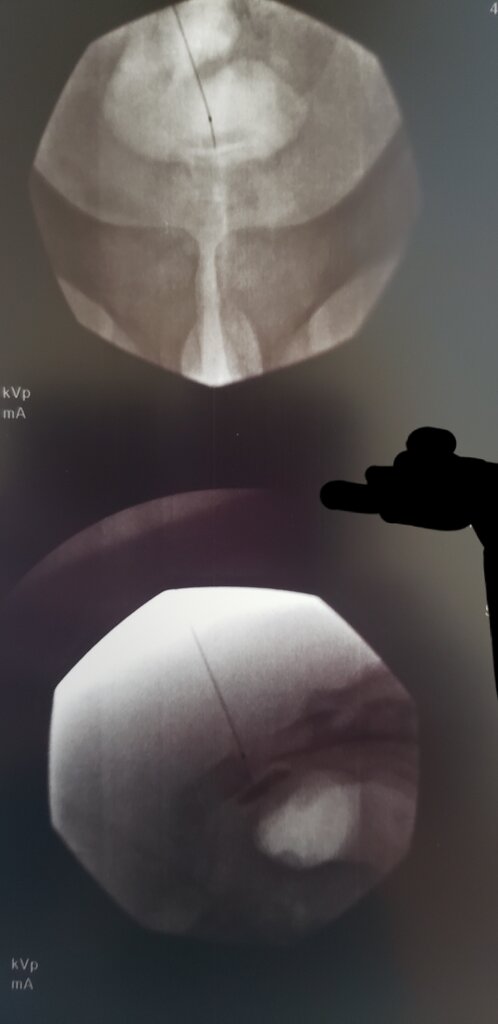

Not too exciting, its just a field block. AP to make sure you're midline, advance in lateral to os and inject. I normally do 20mg triamcinolone and 1mL of 0.25% bupivicaine. Can use point of maximal tenderness to help guide how far cephalad/caudad you inject. I generally inject a little bit at 2-3 sites up and down the field.